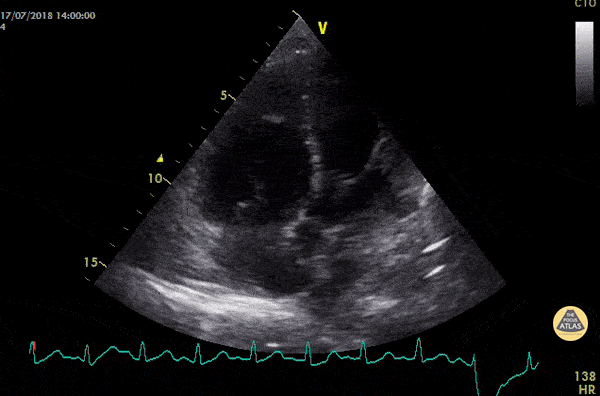

Right Ventricular Dysfunction - Acute PE with McConnell's Sign

46 year old man, intraoperative cardiac arrest after massive pulmonary embolism. Apical four chamber view obtained after resuscitation showed McConnell's sign. We found other signs of acute cor pulmonale : the 60/60 sign and RV dilatation. Dr. Devigne